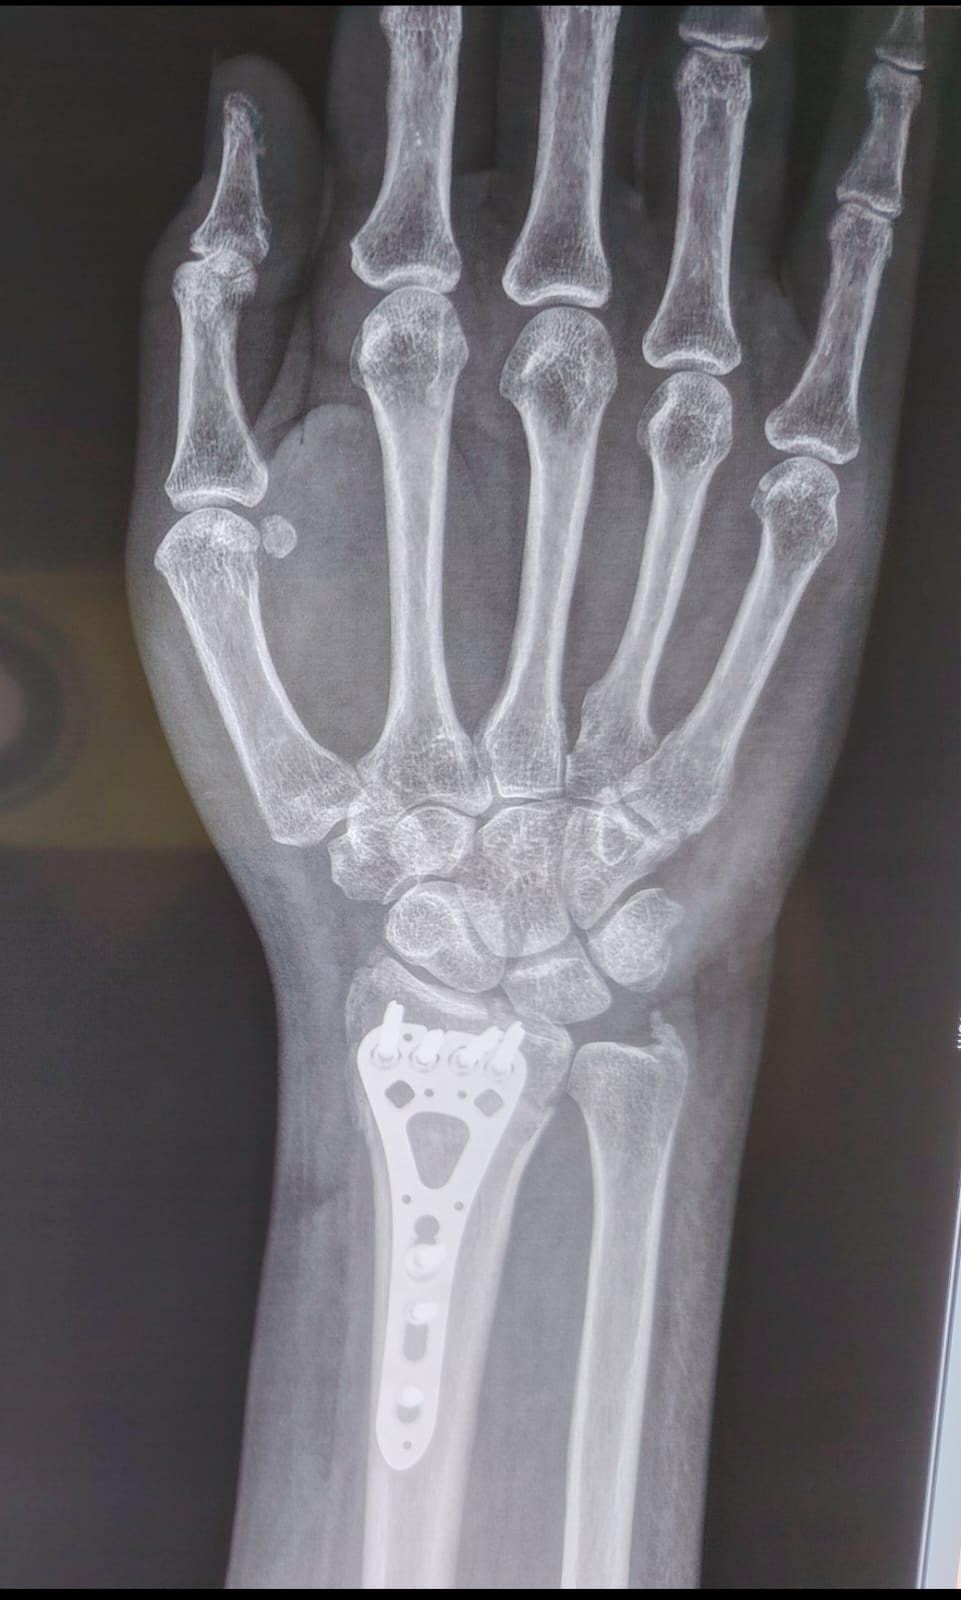

Fractura de muñeca manejada con placa de última generación.